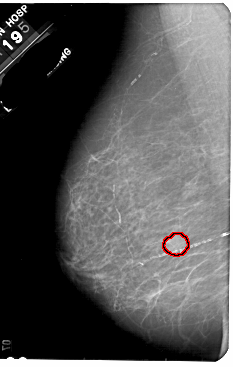

A_1836_1.RIGHT_CC

RIGHT_CC LINES 5491 PIXELS_PER_LINE 3181 BITS_PER_PIXEL 12 RESOLUTION 43.5 NON_OVERLAY

FILE: A_1836_1.LEFT_MLO.OVERLAY

TOTAL_ABNORMALITIES 1

ABNORMALITY 1

LESION_TYPE MASS SHAPE OVAL MARGINS OBSCURED

ASSESSMENT 3

SUBTLETY 5

PATHOLOGY BENIGN

TOTAL_OUTLINES 1